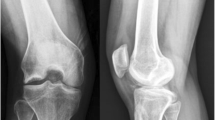

The study was designed with four groups (A, B, C, D; n = 5) to evaluate four different hydrogels as well as hUCB-MSC adding values. The ‘experimental knee’ (right knee) in each group was transplanted with hUCB-MSC + hydrogel and the ‘control knee’ (left knee) in each group was transplanted with hydrogel only. The four different hydrogels were: group A, 4% hyaluronic acid; group B, 3% alginate:30% pluronic (1:1, v/v); group C, 4% hyaluronic acid:3% alginate:20% pluronic (2:1:1, v/v); and group D, 4% hyaluronic acid:3% alginate:20% pluronic: chitosan (4:1:1:2, v/v). Anesthesia was induced by inhalation of 5% ether followed by an intraperitoneal injection of xylazine 10 mg/kg and ketamine 20 mg/kg. In each case, after cleaning with 10% betadine solution, both knee joints of each rat were sterilely draped and opened using an anteromedial approach. The patellae were laterally dislocated, and full-thickness articular cartilage defects (2 mm in diameter) were created in trochlear grooves by carefully drilling in a vertical direction using a 2-mm drill. Drilling was performed 3 mm deep through subchondral bone (Figure 1A). After removing cartilage and bone debris, boundaries around the drill were trimmed using a surgical knife and washed out. The mixture of hUCB-MSCs (1.0 × 107 cells/mL) and different hydrogels was then transplanted into the full-thickness defect in the experimental knee and hydrogel only into the control knee using a syringe.

Articular cartilage defects in a rat model and gross appearance and scoring result at 16 weeks post-transplantation. (A) Gross photos of articular cartilage defects in a rat model. A) The patella was laterally dislocated and full-thickness articular cartilage defects (2 mm diameter) were created through subchondral bone in the trochlear groove in each hindlimb. B) After removing cartilage and bone debris, composites of hUCB-MSCs and different hydrogels were transplanted into defects. (B) Gross findings of repair tissue at articular cartilage defects in rat knees. At 16 weeks postoperatively, tissue defects in hUCB-MSC transplanted knees were repaired to almost the normal level, and border regions between repair and normal tissue were less distinct than those in corresponding control knees. No significant macroscopic differences were observed between the four different hydrogel groups. (C) Gross appearance scores of experimental and control knees in four different hydrogel groups (n = 5/group, *P <0.05).